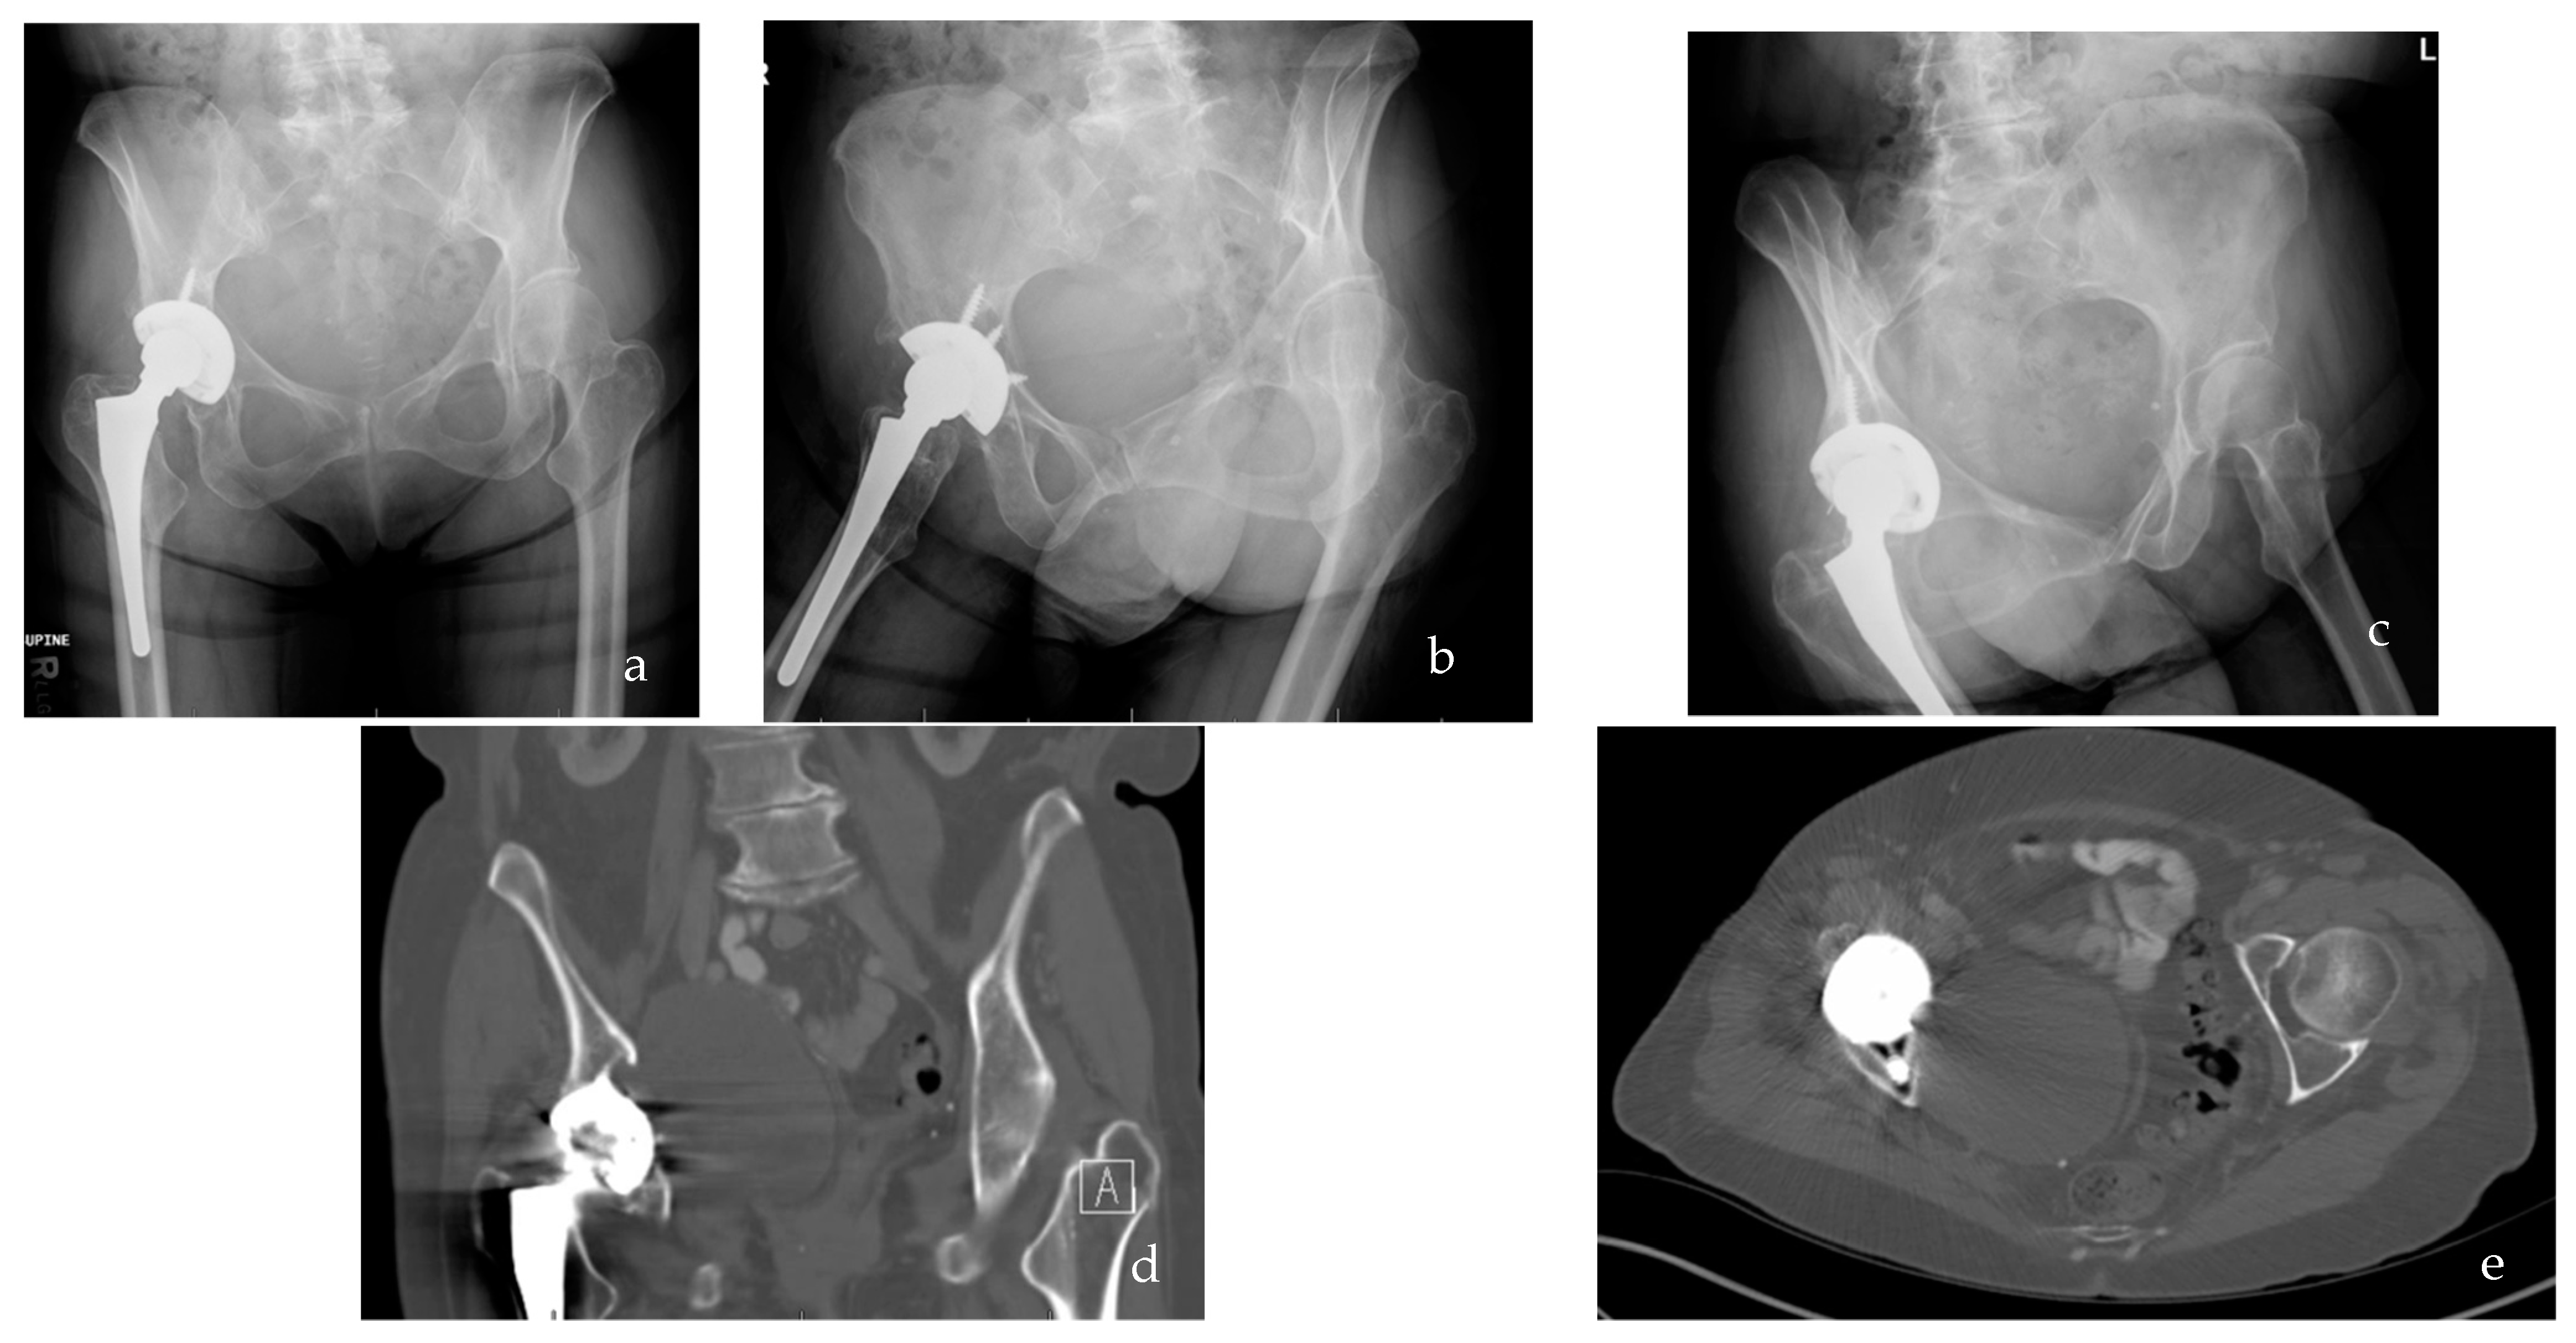

:1. Introduction

2. Innate Immune Response to Wear Debris Particles

2.2. Toll-like Receptors